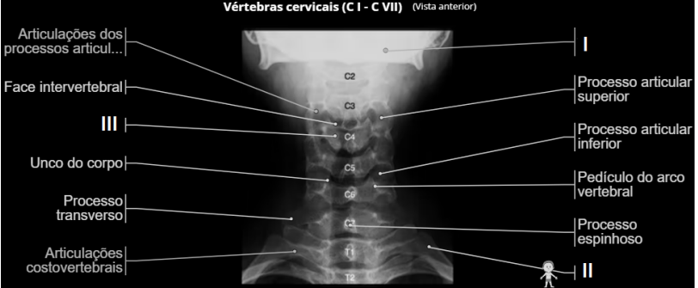

Observe a radiografia das vértebras cervicais (CI – CVII)

Fonte: https://www.imaios.com/br/e-anatomy/coluna-vertebral/radiografias-da-coluna

Anatomicamente os números representados por I, II e III são respectivamente: